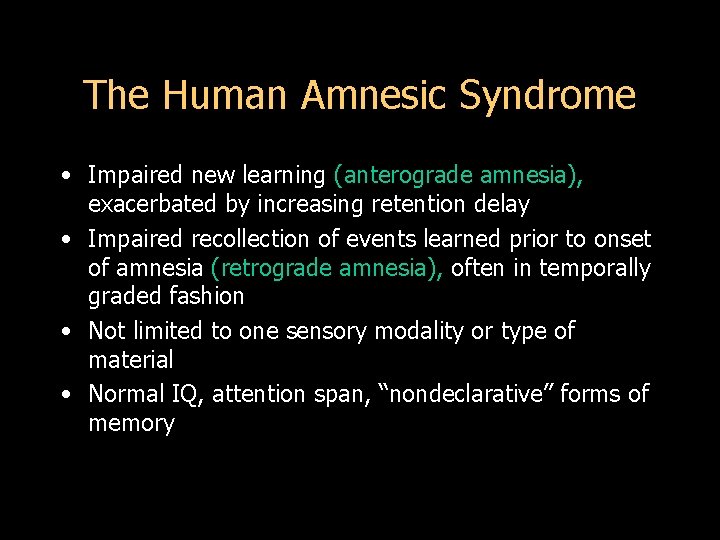

The Human Amnesic Syndrome • Impaired new learning (anterograde amnesia), exacerbated by increasing retention delay • Impaired recollection of events learned prior to onset of amnesia (retrograde amnesia), often in temporally graded fashion • Not limited to one sensory modality or type of material • Normal IQ, attention span, “nondeclarative” forms of memory